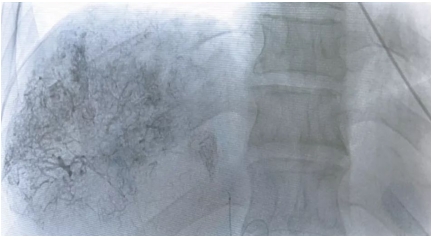

▲圖2 ▲圖3

圖2、圖3 經(jīng)肝動脈造影,顯示腫瘤供養(yǎng)血管,精確超選靶血管進行治療。

▲圖4 ▲圖5

圖4、微導管超選擇至胰十二指腸上動脈行灌注化療

圖5、微導管超選擇至肝動脈腫瘤靶血管行灌注化療,局部藥物濃度是靜脈注射藥物濃度400倍。